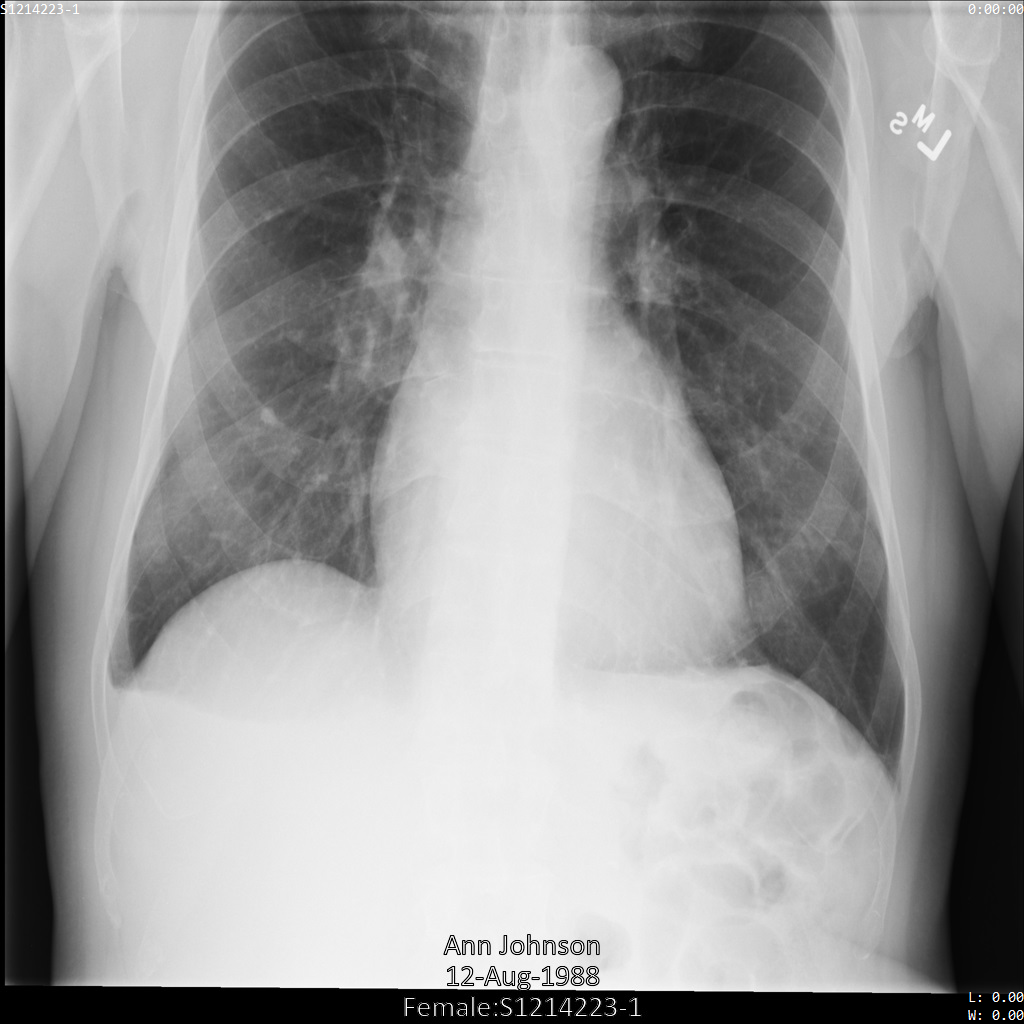

En cada una de las siguientes secciones, se proporcionan ejemplos de cómo desidentificar datos de DICOM mediante varios métodos. Se proporciona un resultado de la imagen desidentificada en cada muestra. En cada muestra, se usa la siguiente imagen original como su entrada:

Puedes comparar la imagen de salida de cada operación de desidentificación con esta imagen original para ver los efectos de la operación.

Después de enviar la imagen a la API de Cloud Healthcare, la imagen aparece de la siguiente manera. De las etiquetas proporcionadas en la removelist, solo se quita PatientBirthDate en la imagen, ya que es la única etiqueta de la lista de eliminación que corresponde a los metadatos visibles en la imagen.

Si bien PatientBirthDate en la esquina superior de la imagen se ocultó de acuerdo con la configuración de la removelist, la PHI de efecto quemado que se encuentra en la parte inferior de la imagen permanece. Para quitar también el texto quemado, consulta Cómo ocultar el texto quemado de las imágenes.